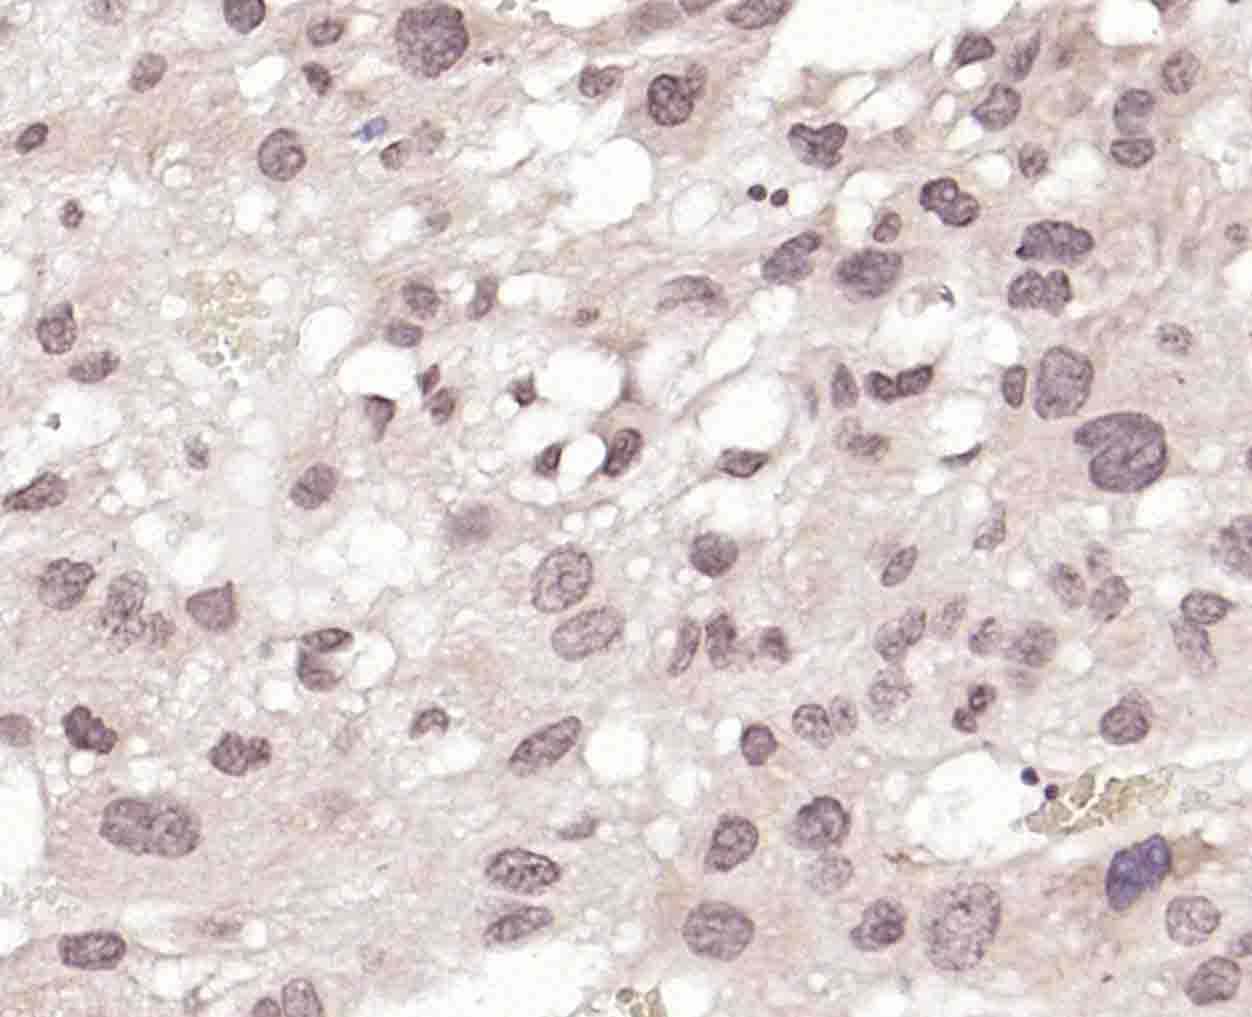

Paraformaldehyde-fixed, paraffin embedded (mouse brain); Antigen retrieval by boiling in sodium citrate buffer (pH6.0) for 15min; Block endogenous peroxidase by 3% hydrogen peroxide for 20 minutes; Blocking buffer (normal goat serum) at 37°C for 30min; Incubation with (BRMS1 Rabbit pAb) Polyclonal Antibody, Unconjugated (bs-8686R) at 1:200 overnight at 4°C, followed by operating according to SP Kit(Rabbit) (sp-0023) instructionsand DAB staining.